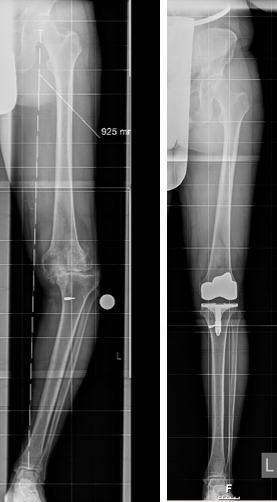

Bild 1: viertgradige und damit höchstgradige Kniearthrose nach einer schweren Verletzung des Kniegelenkes mit massivem O-Bein

Bild 2: Beispiel einer Oberflächenersatz-Endoprothese des Kniegelenkes: Columbus-Oberflächenersatz-Knieendoprothese / Fa. Aesculap, bestehend aus einem Ersatz der Gelenkflächen am Oberschenkelknochen und Unterschenkelknochen. Dazwischen wird eine Polyethylen-Gleitfläche eingebracht.

Bild 3: Ganzbein-Röntgenaufnahme dieses Patienten vor und nach Implantation einer Oberflächenersatz-Knie-Endoprothese mit jetzt korrekter Beinachse